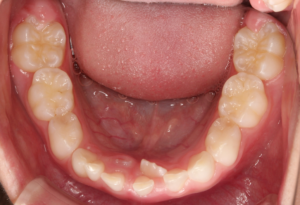

1、なかなか歯が抜けない、生えてこない。乳歯の裏から永久歯が生えてきた。

・乳歯列期から治療を開始することをおすすめします。

一番多いのが、乳歯がなかなか抜けない。抜けて一年くらい永久歯が生えてこない。乳歯の裏から永久歯が生えてきた。ということで来院される方は多いです。